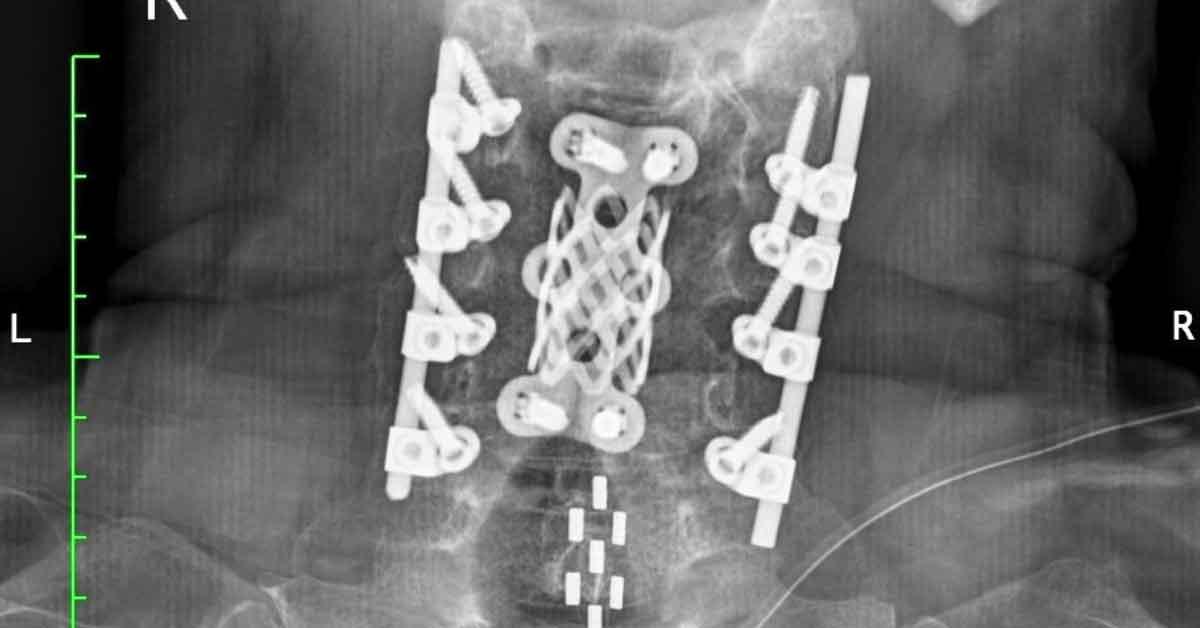

Colpisce anche la vicenda di un giovane che, durante un tuffo in mare in una giornata apparentemente perfetta, ha urtato la testa contro un banco di sabbia. Salvato e trasportato in elicottero in ospedale, ha ricevuto la diagnosi di frattura cervicale, con la concreta possibilità di non camminare più. Dopo l’intervento chirurgico e la fase acuta, sono seguiti mesi in un’unità di riabilitazione spinale, durante i quali ha imparato a vivere con catetere, controllo intestinale complesso e ausili. Tornato a casa dopo dieci mesi, ha affrontato la realtà domestica – più silenziosa ma anche più impegnativa – con obiettivi mensili chiari: salire in auto, trasferirsi dal letto alla sedia, gestire in autonomia la quotidianità.